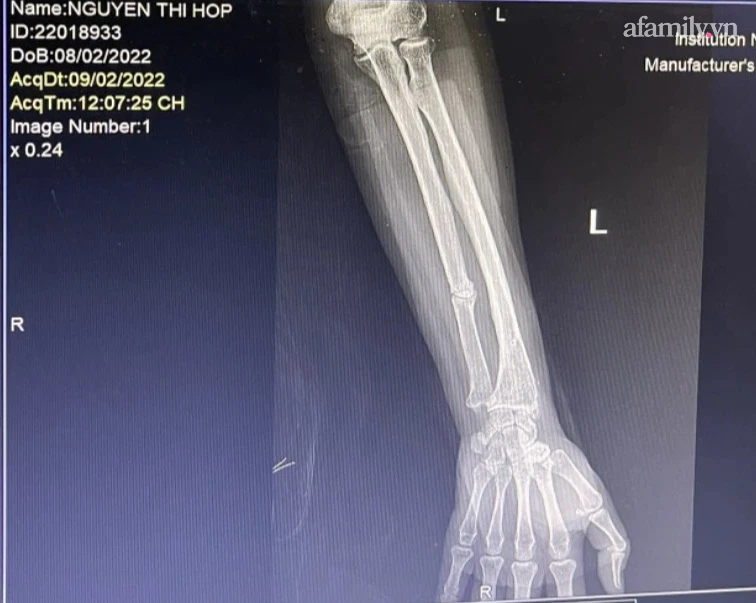

Phim chụp X quang tại bệnh viện

"Không chỉ dùng vũ lực khống chế tay chân, lôi bà Hợp ra ngoài mà chúng còn đánh, đấm, giật tóc, tát và bẻ tay Hợp, làm cho Hợp bị gãy xương tay rồi ném Hợp giữa đường (Khu vực ao làng cạnh cổng chợ Ninh Hiệp). Hiện, Hợp đang phải bó bột và chờ phẫu thuật xương tại bệnh viện"